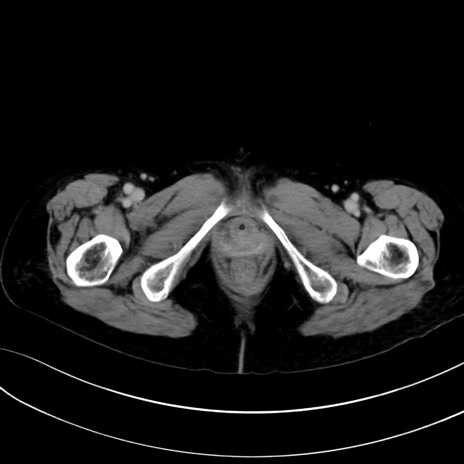

(冠状断像)1日半後